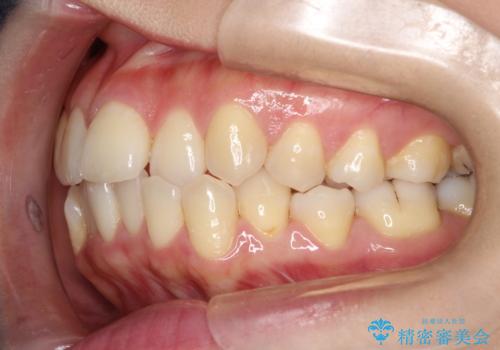

前歯が前後反対にかんでいる インビザラインによる目立たない矯正

- 前歯のかみ合わせを主訴に来院されました。

なるべく目立たずに矯正をしたいとのことで、インビザラインで矯正をすることとしました。

歯と歯の間をわずかに削り、ガタガタを改善しました。

目立たずに矯正を終えることができて、喜んでいただけました。